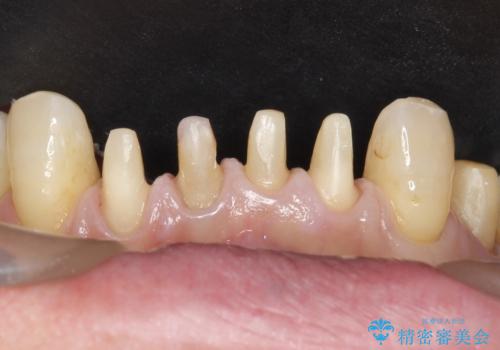

- 下の前歯が欠けてぐらぐらすることを主訴に来院された患者様です。

以前行った奥歯の治療により下顎前歯の動揺は改善傾向にあり顕著ではなかったのですが、欠けて黒くなっていることと少しの動揺が気になるとのことでした。

元気なうちに治療しておきたいという患者様の強いご希望により、下顎前歯の連結補綴と欠けている小臼歯の補綴治療を行いました。